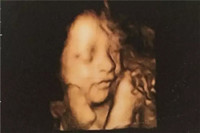

懷孕六個(gè)月男胎兒有多大,懷孕六個(gè)月按孕周期來計(jì)算的話,即是懷孕21周-懷孕24周,此時(shí)的胎兒體重開始大幅度的增加,看上去已經(jīng)很象小寶寶的樣子了,不過皮膚依然是皺的,紅紅的,樣子像閱讀全文>>

六個(gè)月的胎兒長(zhǎng)成什么樣子,他在四肢,五官,胎長(zhǎng)方面都增長(zhǎng)了多少呢?還有懷孕進(jìn)入六個(gè)月時(shí),孕婦會(huì)里而感覺便秘,腰酸背痛的情況,其實(shí)那是你沒有遵守此階段的注意事項(xiàng)。如果你還不...閱讀全文>>